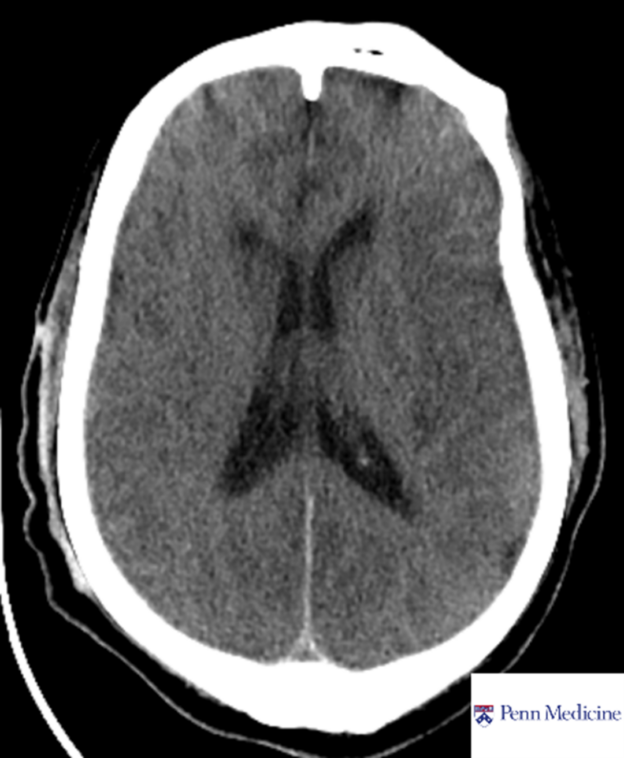

80-year-old man found unconscious

An 80-year-old man was found down and unconscious.